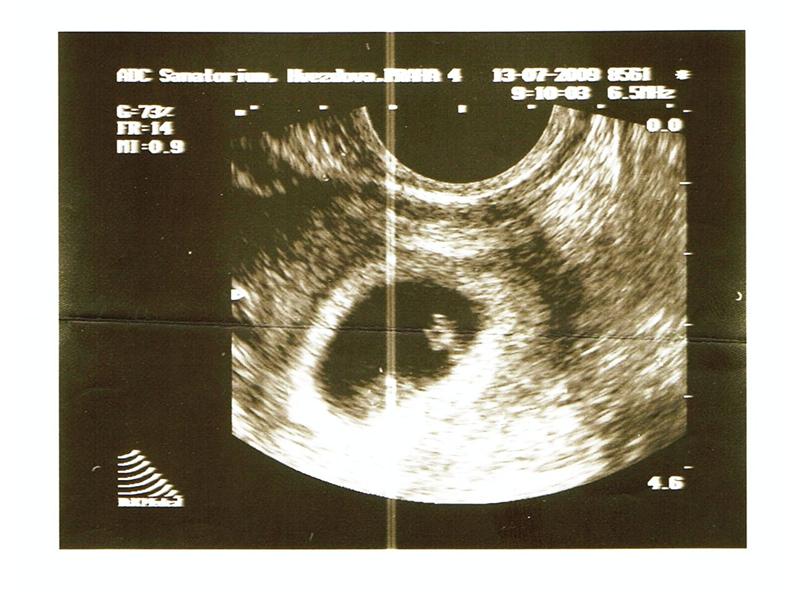

4-12 týden

2 fotografií